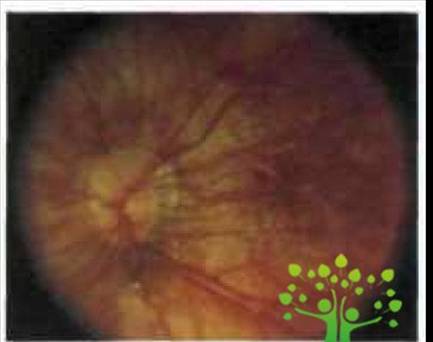

Центральные хориоретинальные дистрофии (ЦХРД) При миопии — это «сухая» (атрофическая) и «влажная» (транссудативная) дистрофии лаковые трещины, центральное пигментное пятно Фукса.

Сухая форма ЦХРД характеризуется вначале побледнением глазного дна вследствие частичной утраты пигментного эпителия и хориокапиллярного слоя (рис. 2).

Рис. 2. Диффузная хориоретинальная атрофия заднего полюса(www.glazmed.ru)

Атрофия этих слоев делает видимыми при офтальмоскопии крупные сосуды хороидеи. Это создает картину так называемого мозаичного глазного дна. По мере прогрессирования процесса запустевают мелкие, средние и крупные сосуды хороидеи. Истончение нейросенсорной сетчатки в макулярной зоне, ее атрофия, особенно при формировании стафиломы, приводят к выпрямлению ретинальных сосудов и уменьшению или исчезновению желтой окраски макулы. Не редко при дегенеративной миопии отмечают аномальное распределение хороидальных вен. Водоворотоподобные вены, хорошо видимые через истонченные ткани, могут пересекать макулярную зону или окружать ДЗН.[9]

Описанная картина представляет собой диффузную хориоретинальную атрофию и может затрагивать весь задний полюс, а также периферию глазного дна в макуле и парамакулярно, а также вокруг ДЗН вначале могут появляться мелкие окружности белого цвета очажки, иногда с пигментированными краями: развивается очаговая хориоретинальная атрофия (рис. 3).